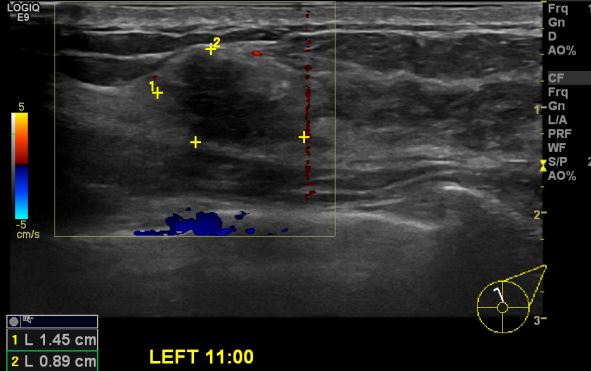

상기환자 양측유두 가려움 증상과 만져지는 멍울있어 내원하신 40대 여성분으로 본원 초음파상 좌측 11시 방향 만져지는 멍울 조직검사 시행하여 비정형유관증식증 관측되어

진공보조유방종양절제술 시행하여 좌측 침윤성 유관암 진단되었습니다.